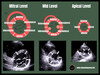

what are you expected to visualise from parasternal long axis view (actual echo image)

A

1. aortic valve:

- use colour doppler to assess for stenosis/ regurgitation

2. mitral valve:

3. LA/LV/Ascending aorta dimensions

4. RV outflow tract

5. Pericardial effusion